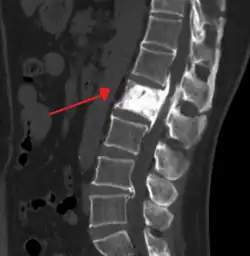

Initially, there is a marked increase in the rate of bone resorption in localized areas, caused by large and numerous osteoclasts. Radiographs at this phase show lucency in the affected bone. These localized areas of pathological destruction of bone tissue (osteolysis) are seen radiologically as an advancing lytic wedge in long bones or the skull. When this occurs in the skull, it is called osteoporosis circumscripta. The osteolysis is followed by a compensatory increase in bone formation and increase in alkaline phosphatase levels induced by the bone-forming cells, called osteoblasts, that are recruited to the area. This is associated with accelerated deposition of lamellar bone in a disorganized fashion. Woven bone, rather than lamellar bone, predominates and mineralization occurs at twice the normal rate.[5] This intense cellular activity produces a chaotic picture of trabecular bone ("mosaic" pattern), rather than the normal linear lamellar pattern. The resorbed bone is replaced and the marrow spaces are filled by an excess of fibrous connective tissue with a marked increase in blood vessels, causing the bone to become hypervascular. The bone hypercellularity may then diminish, leaving a dense "pagetic bone", also known as burned-out Paget's disease. A later phase of the disease is characterized by the replacement of normal bone marrow with highly vascular fibrous tissue.[25]